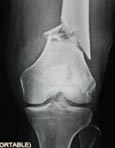

JOINT REPLACEMENT

• Over 22 years experience in Knee, Hip, Shoulder and Elbow joint replacements

• Introduced Computer navigation joint Replacement in Eastern India